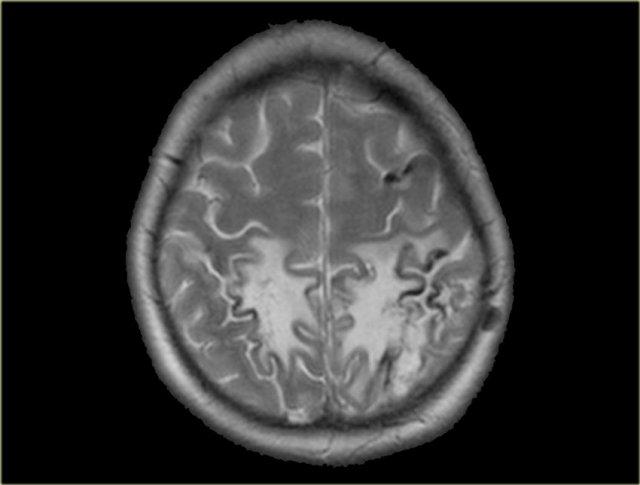

Mất tín hiệu trống dòng chảy bình thường trên MRI

Trên các chuỗi xung spin-echo, các tĩnh mạch não thông thoáng thường biểu hiện giảm tín hiệu do hiện tượng trống dòng chảy (flow void).

Tín hiệu trống dòng chảy thấy rõ nhất trên chuỗi xung T2W và FLAIR, nhưng đôi khi cũng có thể thấy trên chuỗi xung T1W.

Huyết khối sẽ biểu hiện bằng sự vắng mặt của tín hiệu trống dòng chảy.

Mặc dù đây không phải là dấu hiệu hoàn toàn đáng tin cậy, nhưng thường là một trong những dấu hiệu đầu tiên khiến ta nghĩ đến khả năng huyết khối tĩnh mạch.

Bước tiếp theo cần thực hiện là chụp có tiêm thuốc tương phản từ.

Hình ảnh bên trái là chuỗi xung T2W với tín hiệu trống dòng chảy bình thường ở xoang sigma phải và tĩnh mạch cảnh trong phải (mũi tên xanh dương).

Bên trái có tín hiệu cao bất thường là kết quả của huyết khối (mũi tên đỏ).